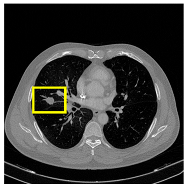

3.4.2. Representative Cases with Segmentation Challenges on the MEF-PN35 Dataset

To complement the quantitative evaluation, we present a set of representative cases from the clinical dataset that exhibited typical segmentation challenges. These cases were selected to reflect diverse morphological characteristics observed in pulmonary nodules, such as spiculated boundaries, small size, vessel adherence, pleural attachment, cavitation, and clear isolation. Rather than aiming for exhaustive categorization, our intent is to highlight a range of practical difficulties encountered in real-world scenarios and to qualitatively assess how different boundary-aware loss functions respond to these variations. Each challenge is labeled (C1) through (C5) in Table 10 and is consistently referenced in the corresponding detailed illustrations that follow.

Following the summary in Table 11, we present detailed visual comparisons for selected representative cases, each corresponding to a specific segmentation challenge. These cases are consistently labeled using the Challenge ID (CID) codes defined in Table 9 to facilitate cross-referencing between the summary and the case illustrations. Each table reports segmentation results across three loss configurations (Sobel, Laplacian, and Hausdorff) using five columns. Loss indicates the boundary loss formulation applied in each case, where Dice loss is combined with a boundary term computed using Sobel, Laplacian, or Hausdorff operators. The Segmentation Result column shows four images side by side: the input CT patch, the manual ground truth, the model prediction, and a color-coded difference map between ground truth and prediction. In this map, green indicates true positives, blue represents true negatives, red corresponds to false positives, and yellow denotes false negatives. The final column, Attention Map, presents Grad-CAM visualizations derived from one of the Adaptive Attention Fusion (AAF) layers in the encoder path. These maps illustrate the spatial focus of the model, with red/yellow regions indicating strong attention and lighter or neutral tones indicating lower activation. All six cases are presented in detail in Table 11, Table 12 and Table 13, providing a comprehensive qualitative analysis of how each loss configuration performs under specific segmentation challenges observed in real clinical data.

Beyond quantitative metrics, the model has also demonstrated strong performance across a diverse range of challenging clinical scenarios. As detailed in Table 11, Table 12 and Table 13, CAAF-ResUNet effectively handled representative cases including nodules with clear boundaries (C1), small size (C2), blurred margins (C3a–C3b), cavitary structures (C4), and spiculated edges (C5). These examples underscore the model’s ability to adapt to a wide spectrum of morphological complexities often encountered in routine CT interpretation.